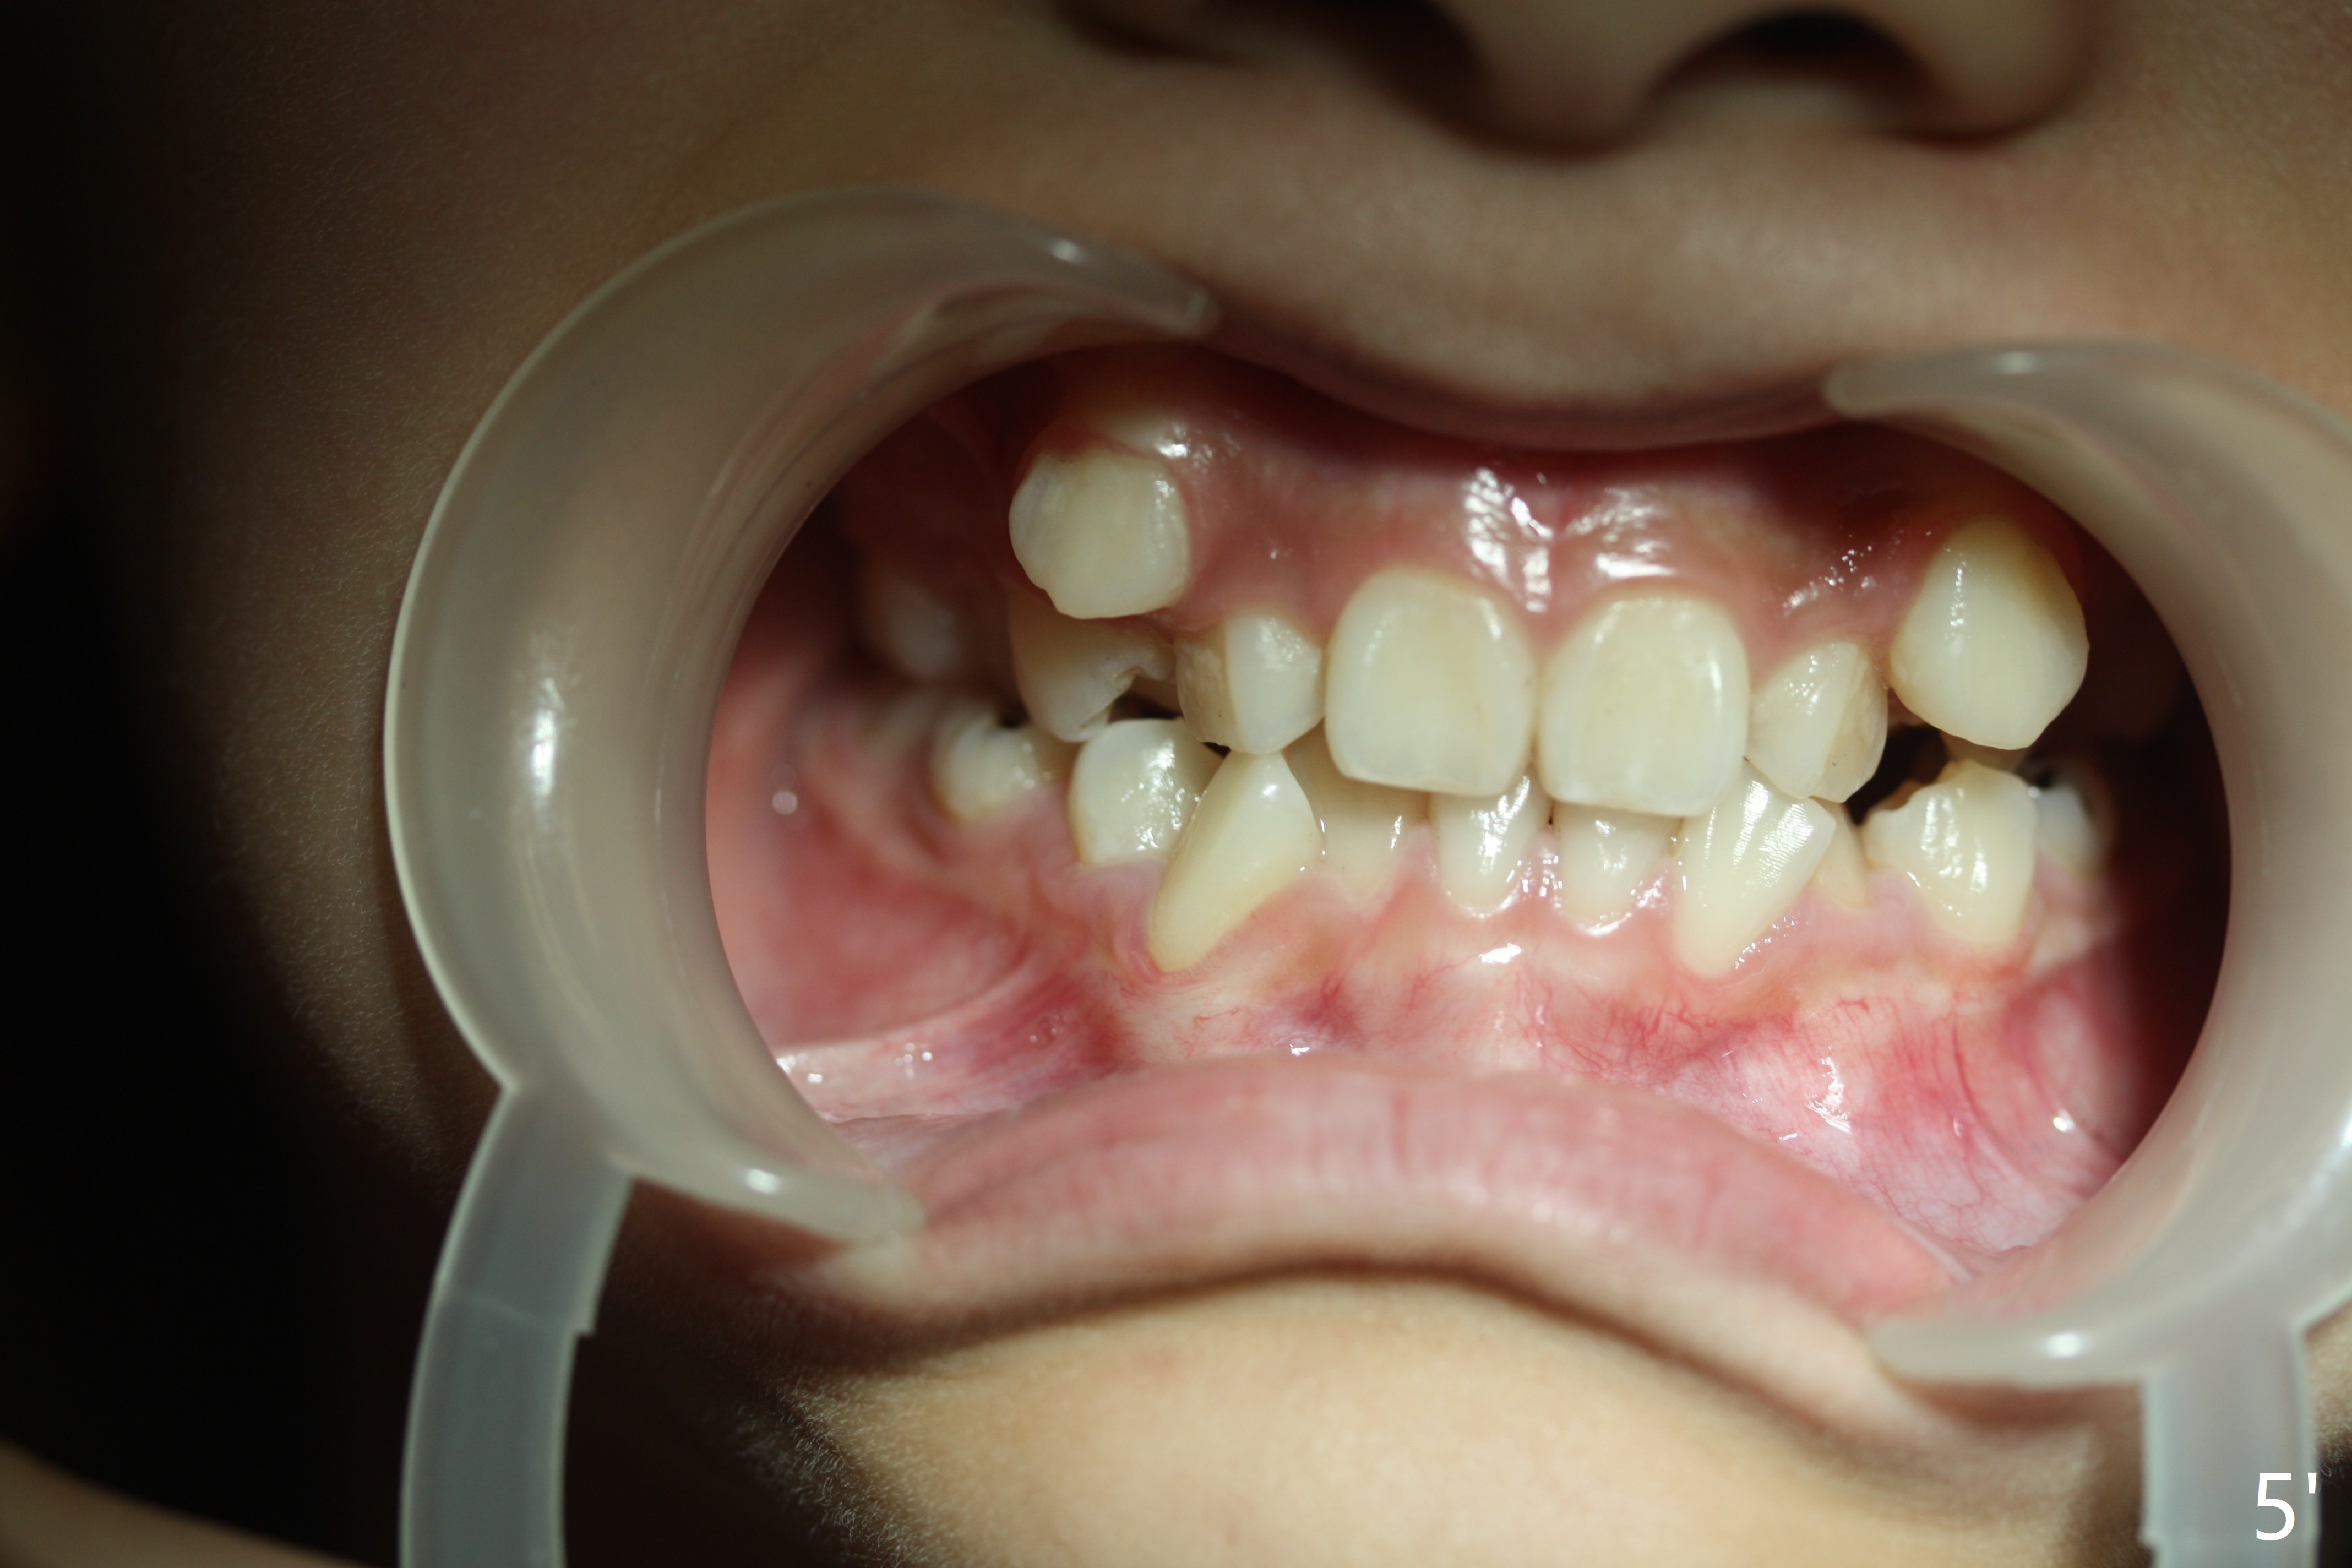

Since U3s are our focus, raise the cheek retractor (Fig.5 vs. 5').  Ask the patient to turn the head to you when taking intraoral photos.  Also pay attention to the occlusal plane (not slant).